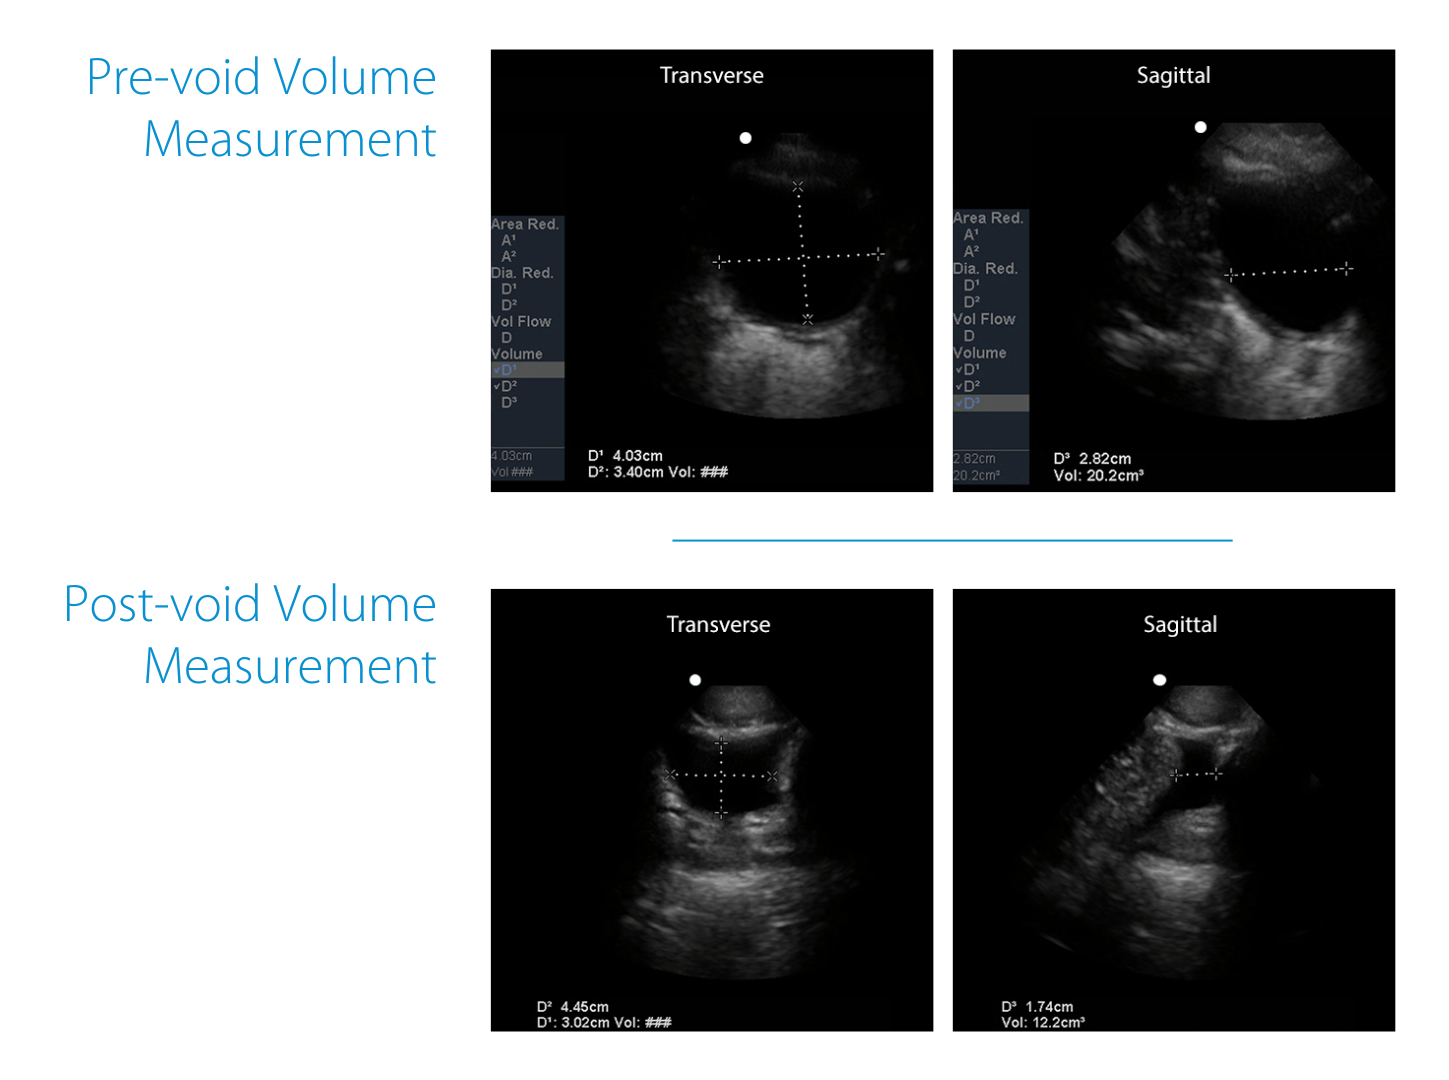

Example from training:

Pre-void volume measured about 20.2 cc.

After the patient attempted to void, repeating the same steps produced a post-void residual of about 12.2 cc.